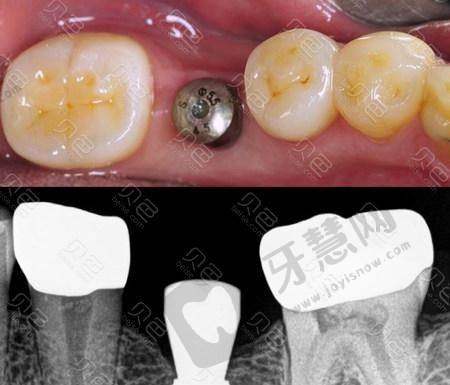

白若飞医生专精能力出色,在口腔领域有着广泛且深入的专精技能。他擅长固定修复、活动修复、种植修复、咬合重建等多个方面。在美学修复上,前牙全瓷贴面美学修复、全瓷冠的美学修复以及牙齿美白都展现出不错技艺,能有效改善患者牙齿外观。对于复杂牙周病、牙体牙髓、疑难根管治疗等病症,他凭借丰富的经验和专精知识,为患者提供精细治疗。此外,微痛拔牙、补牙、系统全方面洁牙以及儿童龋病、牙髓病的治疗也十分擅长,诊疗成效显著,深受患者信赖。

有患者分享了找白若飞医生做牙齿种植手术的感受。手术前患者心里特别紧张,但是白医生一直耐心安慰,给患者讲解手术过程,让患者安心不少。手术时打了麻药一点都不疼,白医生操作熟练,动作轻柔,特别快就完成了种植。术后麻药劲儿过了,稍微有点疼,但在能忍受的范围内。按照白医生的嘱咐进行护理,修复得特别顺利。现在牙齿用着特别好,和真牙没什么区别。患者对白医生的技术和服务都特别满意。